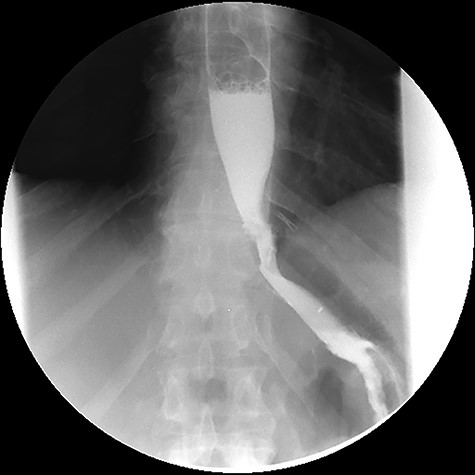

In December 2015, the patient presented to the emergency room complaining of pain in the left hypochondrium and anorexia. Upon physical examination, the only abnormal finding was tenderness to palpation of the left hypochondrium. The laboratory tests revealed an elevated white blood cells count (18.88 × 103/μL) and an elevated C-reactive protein (263.66 mg/L). A CT scan of the abdomen revealed a GGF with an associated abscess (see Fig. 8).

Computed tomography images. A: Image obtained prior to administration of contrast showing an abscess on the left upper quadrant of the abdomen (asterisk). B: Image obtained after administration of oral contrast showing progression of contrast through the gastro-jejunal anastomosis and through the gastro-gastric fistula (arrows).